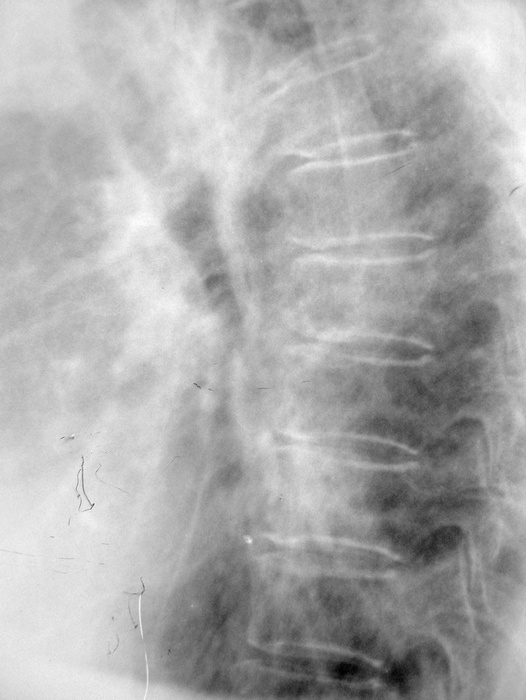

女.80.慢支炎5年.加重1周.请各位会诊

右肺中叶肺不张或阻塞性肺炎+两肺间质纤维化---ct确诊。

考虑慢性支气管炎合并感染,右上继发型肺结核。必要时做ct进一步检查。

右上肺可见片结影,余肺纹增多且模糊,支持慢支并感染,右上肺继发性结核。建议ct。

慢性支气管炎合并感染,双肺上野结核。